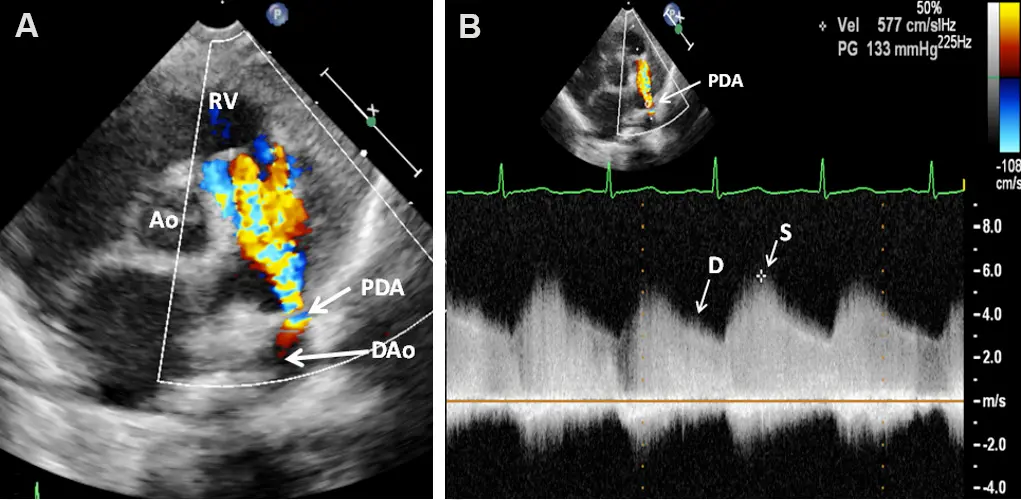

In (A) you see flow going from the proximal descending aorta through the PDA into the proximal left pulmonary artery. In (B) we see spectral doppler showing continuous flow with higher velocities in systole than in diastole. Figure source